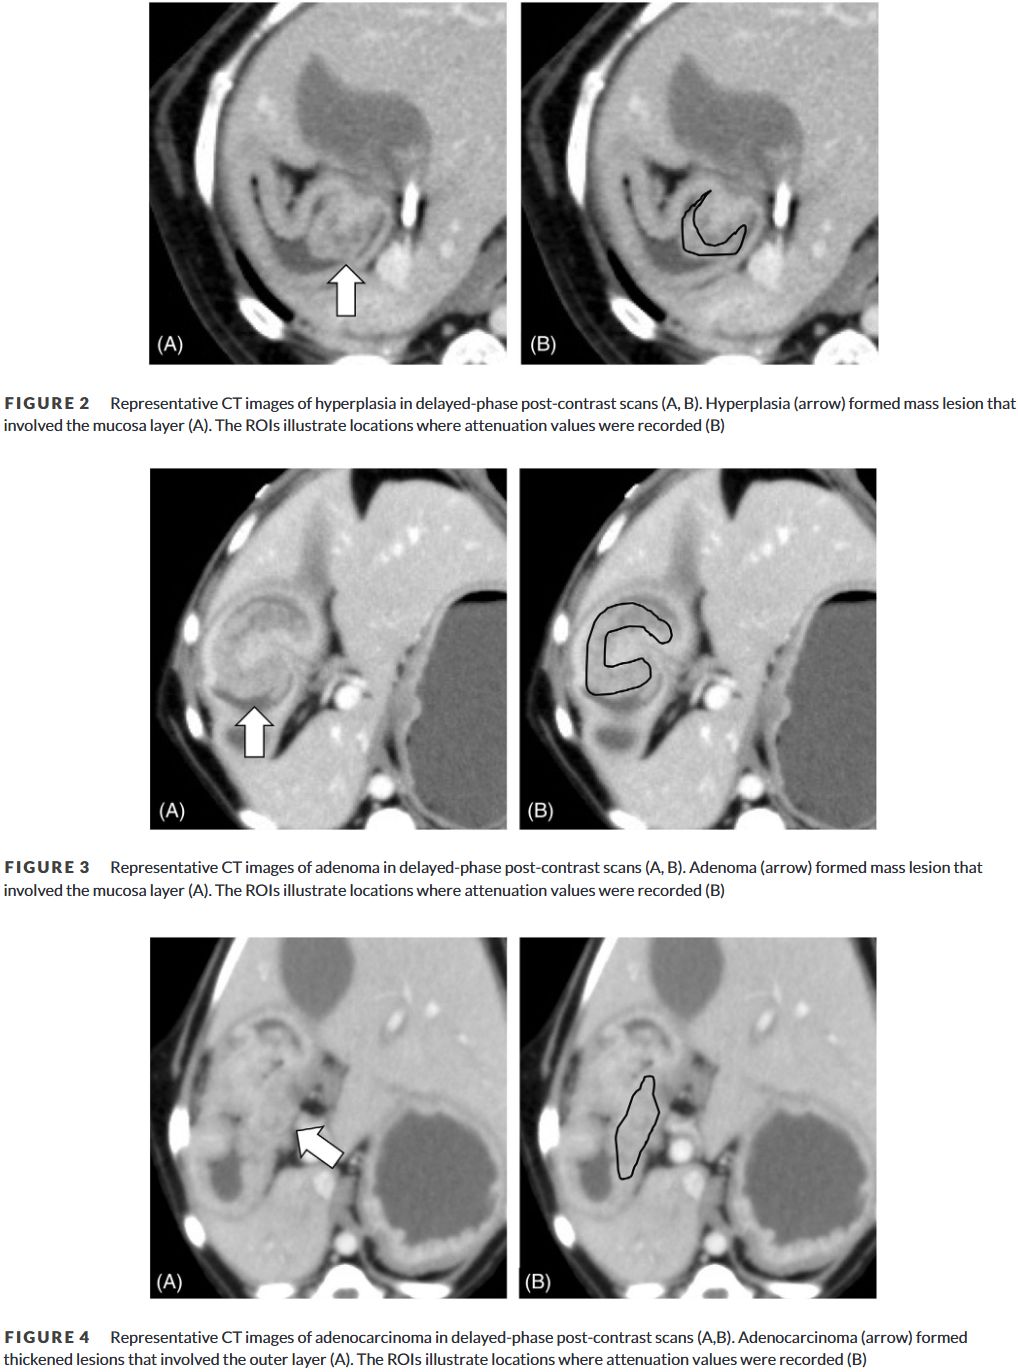

- Hyperplasia and adenoma formed heterogeneous, mucosal mass lesions.

- Adenocarcinomas showed asymmetric wall thickening involving outer layers, with lymph node metastases in all cases.

CT images of hyperplasia, adenoma, adenocarcinoma.